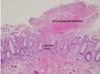

Celiac Disease

Celiac Disease

Celiac Disease